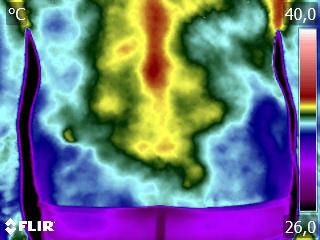

Como no caso do paciente abaixo do sexo masculino, 38 anos, sem comorbidades e que apresentou dor aguda em região lombar. Foi realizada uma Análise Termofuncional e foi detectado alterações térmicas compatíveis com o relato clínico de dor lombar.

Essas informações foram integradas à avaliação fisioterapêutica e, quando analisadas corretamente dentro da técnica, a termografia permite compreender respostas fisiológicas que não aparecem em exames estruturais.